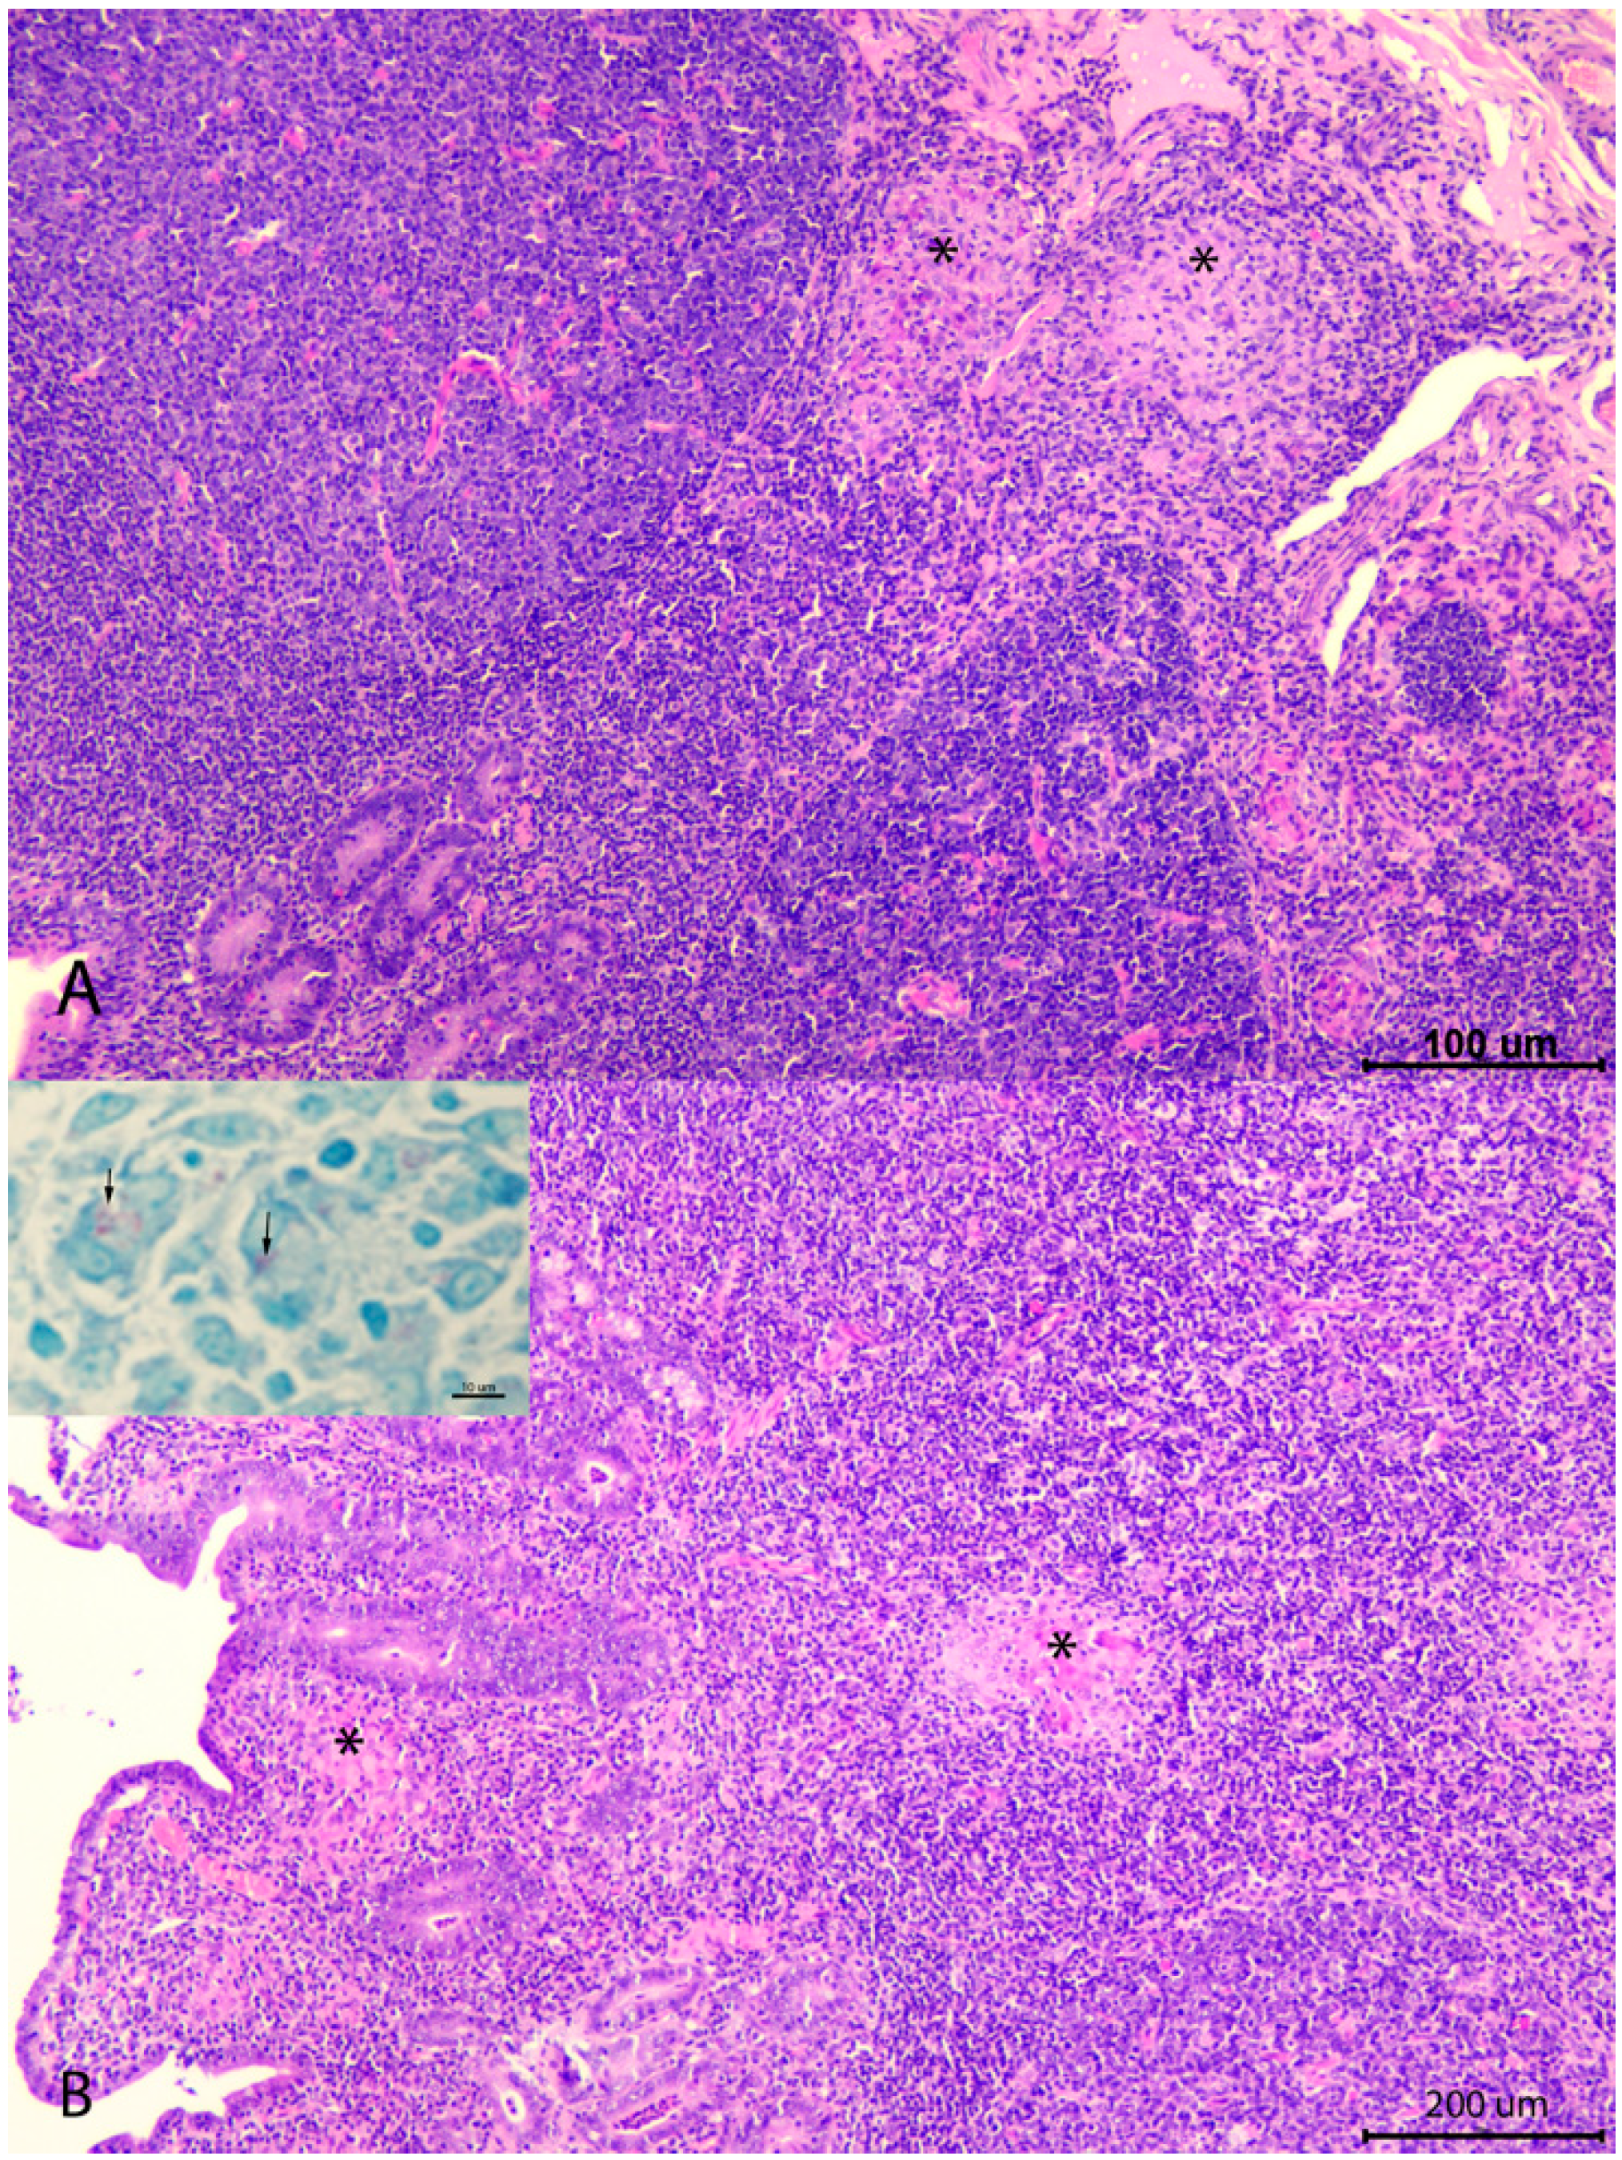

- Corpa, J.; Garrido, J.; García-Marín, J.; Pérez, V. Classification of lesions observed in natural cases of paratuberculosis in goats. J. Comp. Pathol. 2000, 122, 255–265. [Google Scholar] [CrossRef]

- Arteche-Villasol, N.; Gutiérrez-Expósito, D.; Elguezabal, N.; Sevilla, I.A.; Vallejo, R.; Espinosa, J.; Ferreras, M.; Benavides, J.; Pérez, V. Influence of heterologous and homologous vaccines and their components, on the host immune response and protection against experimental caprine paratuberuclosis. Front. Vet. Sci. 2022, 8, 744568. [Google Scholar] [CrossRef]